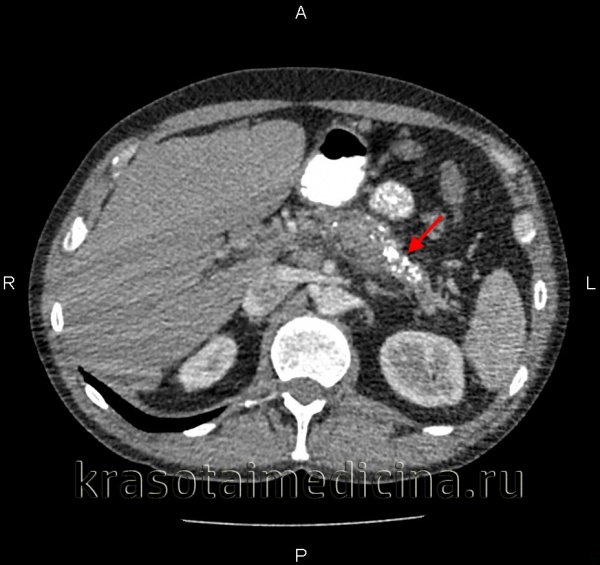

Наиболее информативными инструментальными методами диагностики острого панкреатита являются УЗИ, КТ, МРТ органов брюшной полости. УЗИ остается одним из наиболее доступных и информативных методов исследования. Эта безопасная неинвазивная методика позволяет выявить этиологический фактор острого панкреонекроза (конкременты желчевыводящих путей), отек и участки некроза поджелудочной железы, позволяет дифференцировать жидкостные образования. Но «золотым стандартом» диагностики на современном этапе является компьютерная томография органов брюшной полости. Данная методика позволяет четко визуализировать увеличение поджелудочной железы, очаги некроза, а также наличие осложнений, с высокой достоверностью разграничивать жидкостное скопление от плотных некротических масс. Наличие пузырьков газа в зоне деструкции, определяемое при КТ-исследовании, свидетельствует об инфицировании данного очага.

КТ органов брюшной полости. Множественные кальцинаты в области хвоста и тела поджелудочной железы (последствия множественных острых эпизодов панкреатита)

КТ органов брюшной полости. Панкреатит (в области хвоста поджелудочной железы) с наличием отека ее паренхимы, жидкостного содержимого вблизи ее края, на фоне утолщение фасции Героты слева